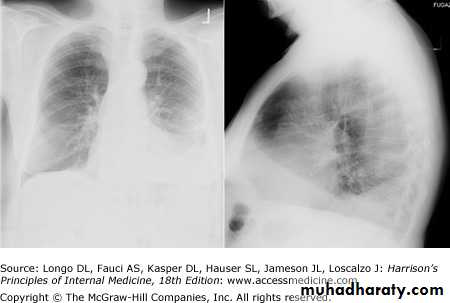

- (CXR) :The classical appearance of pleural fluid on the erect PA chest film is of a curved shadow at the lung base, blunting the costophrenic angle and ascending towards the axilla

Fluid appears to track up the lateral chest wall.

Around 200 mL of fluid is required to be detectable on a PA chest X-ray, but smaller effusions can be identified by ultrasound or CT.

-Ultrasonography is more accurate than plain chest radiography for determining the volume of pleural fluid and frequently provides additional helpful information.

Visualization of fluid facilitates skin marking to indicate a site for safe needle aspiration and guides pleural biopsy, increasing diagnostic yield